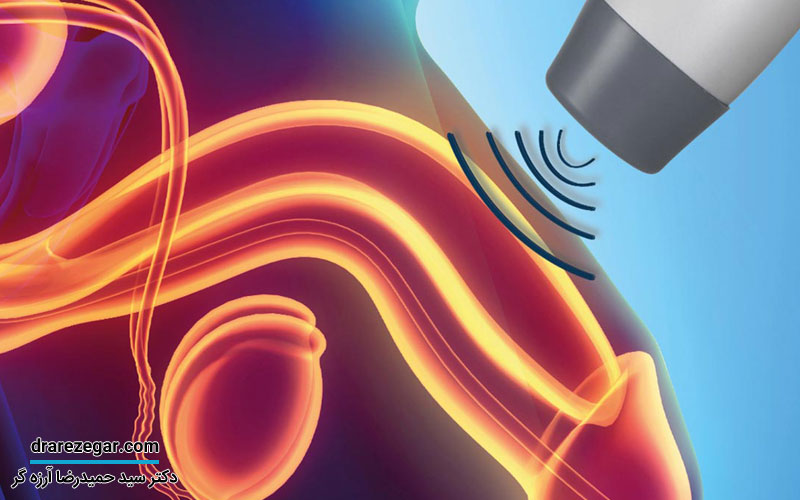

به نظر می رسد که تثبیت کلیه با استفاده از لاپاراسکوپی، یکی از کارآمدترین روش های درمان جراحی باشد. در این روش، تنها یک برش کوچک ایجاد می شود تا جراح به کلیه دسترسی پیدا کند. این روش هنوز به عنوان استاندارد تثبیت کلیه مورد تأیید قرار نگرفته است و نیاز به بیشترین مطالعه و ثبت نتایج برای ارزیابی دقیق تر آن وجود دارد.